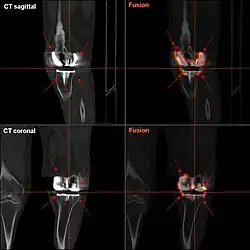

|

Angles commonly measured before knee replacement surgery: |

To indicate knee replacement in case of osteoarthritis, its radiographic classification and severity of symptoms both should be substantial. Such radiography should consist of weightbearing X-rays of both knees: AP, lateral, and 30 degrees of flexion. AP and lateral views may not show joint space narrowing, but the 30-degree flexion view is most sensitive for narrowing. Full-length projections also are used in order to adjust the prosthesis to provide a neutral angle for the distal lower extremity. Two angles used for this purpose are:

- Hip-knee-shaft angle (HKS),[10] an angle formed between a line through the longitudinal axis of the femoral shaft and its mechanical axis, which is a line from the center of the femoral head to the intercondylar notch of the distal femur.[12]

- Hip-knee-ankle angle (HKA),[11] which is an angle between the femoral mechanical axis and the center of the ankle joint.[12] It is normally between 1.0° and 1.5° of varus in adults.[13]